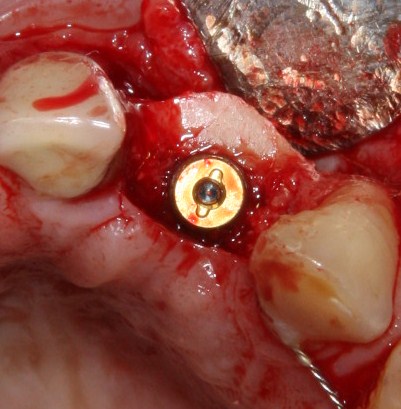

Установка имплантатов

По ряду уже упомянутых выше причин, для решения этой клинической задачи мы выбрали имплантаты Xive. Лунки для них мы уже приготовили. возможную первичную стабильность оценили. Имплантаты мы установили с усилием чуть больше 15-20 Нсм — такого крутящего момента более, чем достаточно, особенно если учесть, что временные коронки будут соединяться между собой.

Подробно о том, что такое крутящий момент и хирургический протокол можно прочитать здесь>> и тут>>, соответственно. Из-за использования специальных индивидуализируемых временных абатментов, имеющих только три положения, нам нужно позиционировать платформу имплантатов по граням. Это очень просто  — мы выводим вырез абатмента TempBase (он входит в комплект поставки) вестибулярно.

После перкуторной проверки стабильности имплантатов и точности позиционирования, мы переходим к следующему этапу — сохранению десневого контура.

Установка имплантатов занимает около двух минут.